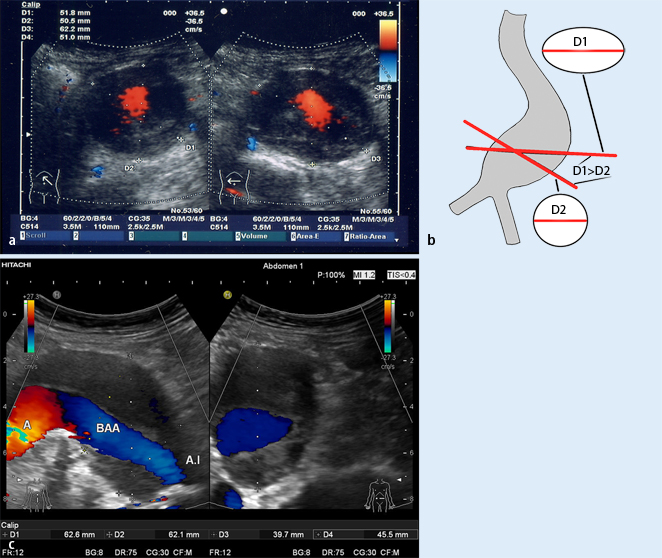

Transducer position and multiplanar reconstruction

Fig. 3

a Aortic diameter in AAA with left-lateral elongation: comparison of the measurement obtained in upper abdominal cross section (right; see body marker) of 62.2 mm (D3) with the measurement of 51.8 mm (D1) when the diameter is turned on the vessel axis at the same point (left). The orthogonal diameter measurement (left) corresponds to the real diameter. The anteroposterior (AP) measurement remains constant (50.5 and 51 mm in D2 and D4, respectively). b Appropriate diameter measurement in AAA with an elongated vessel course. Measuring in abdominal cross section results in a false-high diameter due to the elliptical representation obtained in oblique section of the aneurysmal sack (D1). This measurement often also has low reproducibility, resulting in fluctuations in measured values. In order to obtain appropriate as well as reproducible measurements, the transducer should be turned in the area of maximum diameter in such a way that the real aneurysm transverse diameter (D2) perpendicular to the vessel axis is visualized (often a round structure) (modified from [20]). c A comparison of maximum AAA diameter measurement (ventrolateral elongation) of 62.6 mm (D1) in abdominal cross section in the AP plane (right) with measurement in the orthogonal plane (perpendicular to the vessel axis in longitudinal section; left). The real aortic diameter here is only a maximum of 45.5 mm (D4); at the measurement point in the AP transverse plane, it is only 39.7 mm (D3). The measurement of 62.1 mm in cross section (right) is also marked with measuring marks (D2) in the longitudinal section (left). Diameter measurement in the AP plane in the right-hand section of the image corresponds to the AP measurement on CT in an axial plane (without reconstruction). BAA abdominal aortic aneurysm, A.I iliac artery